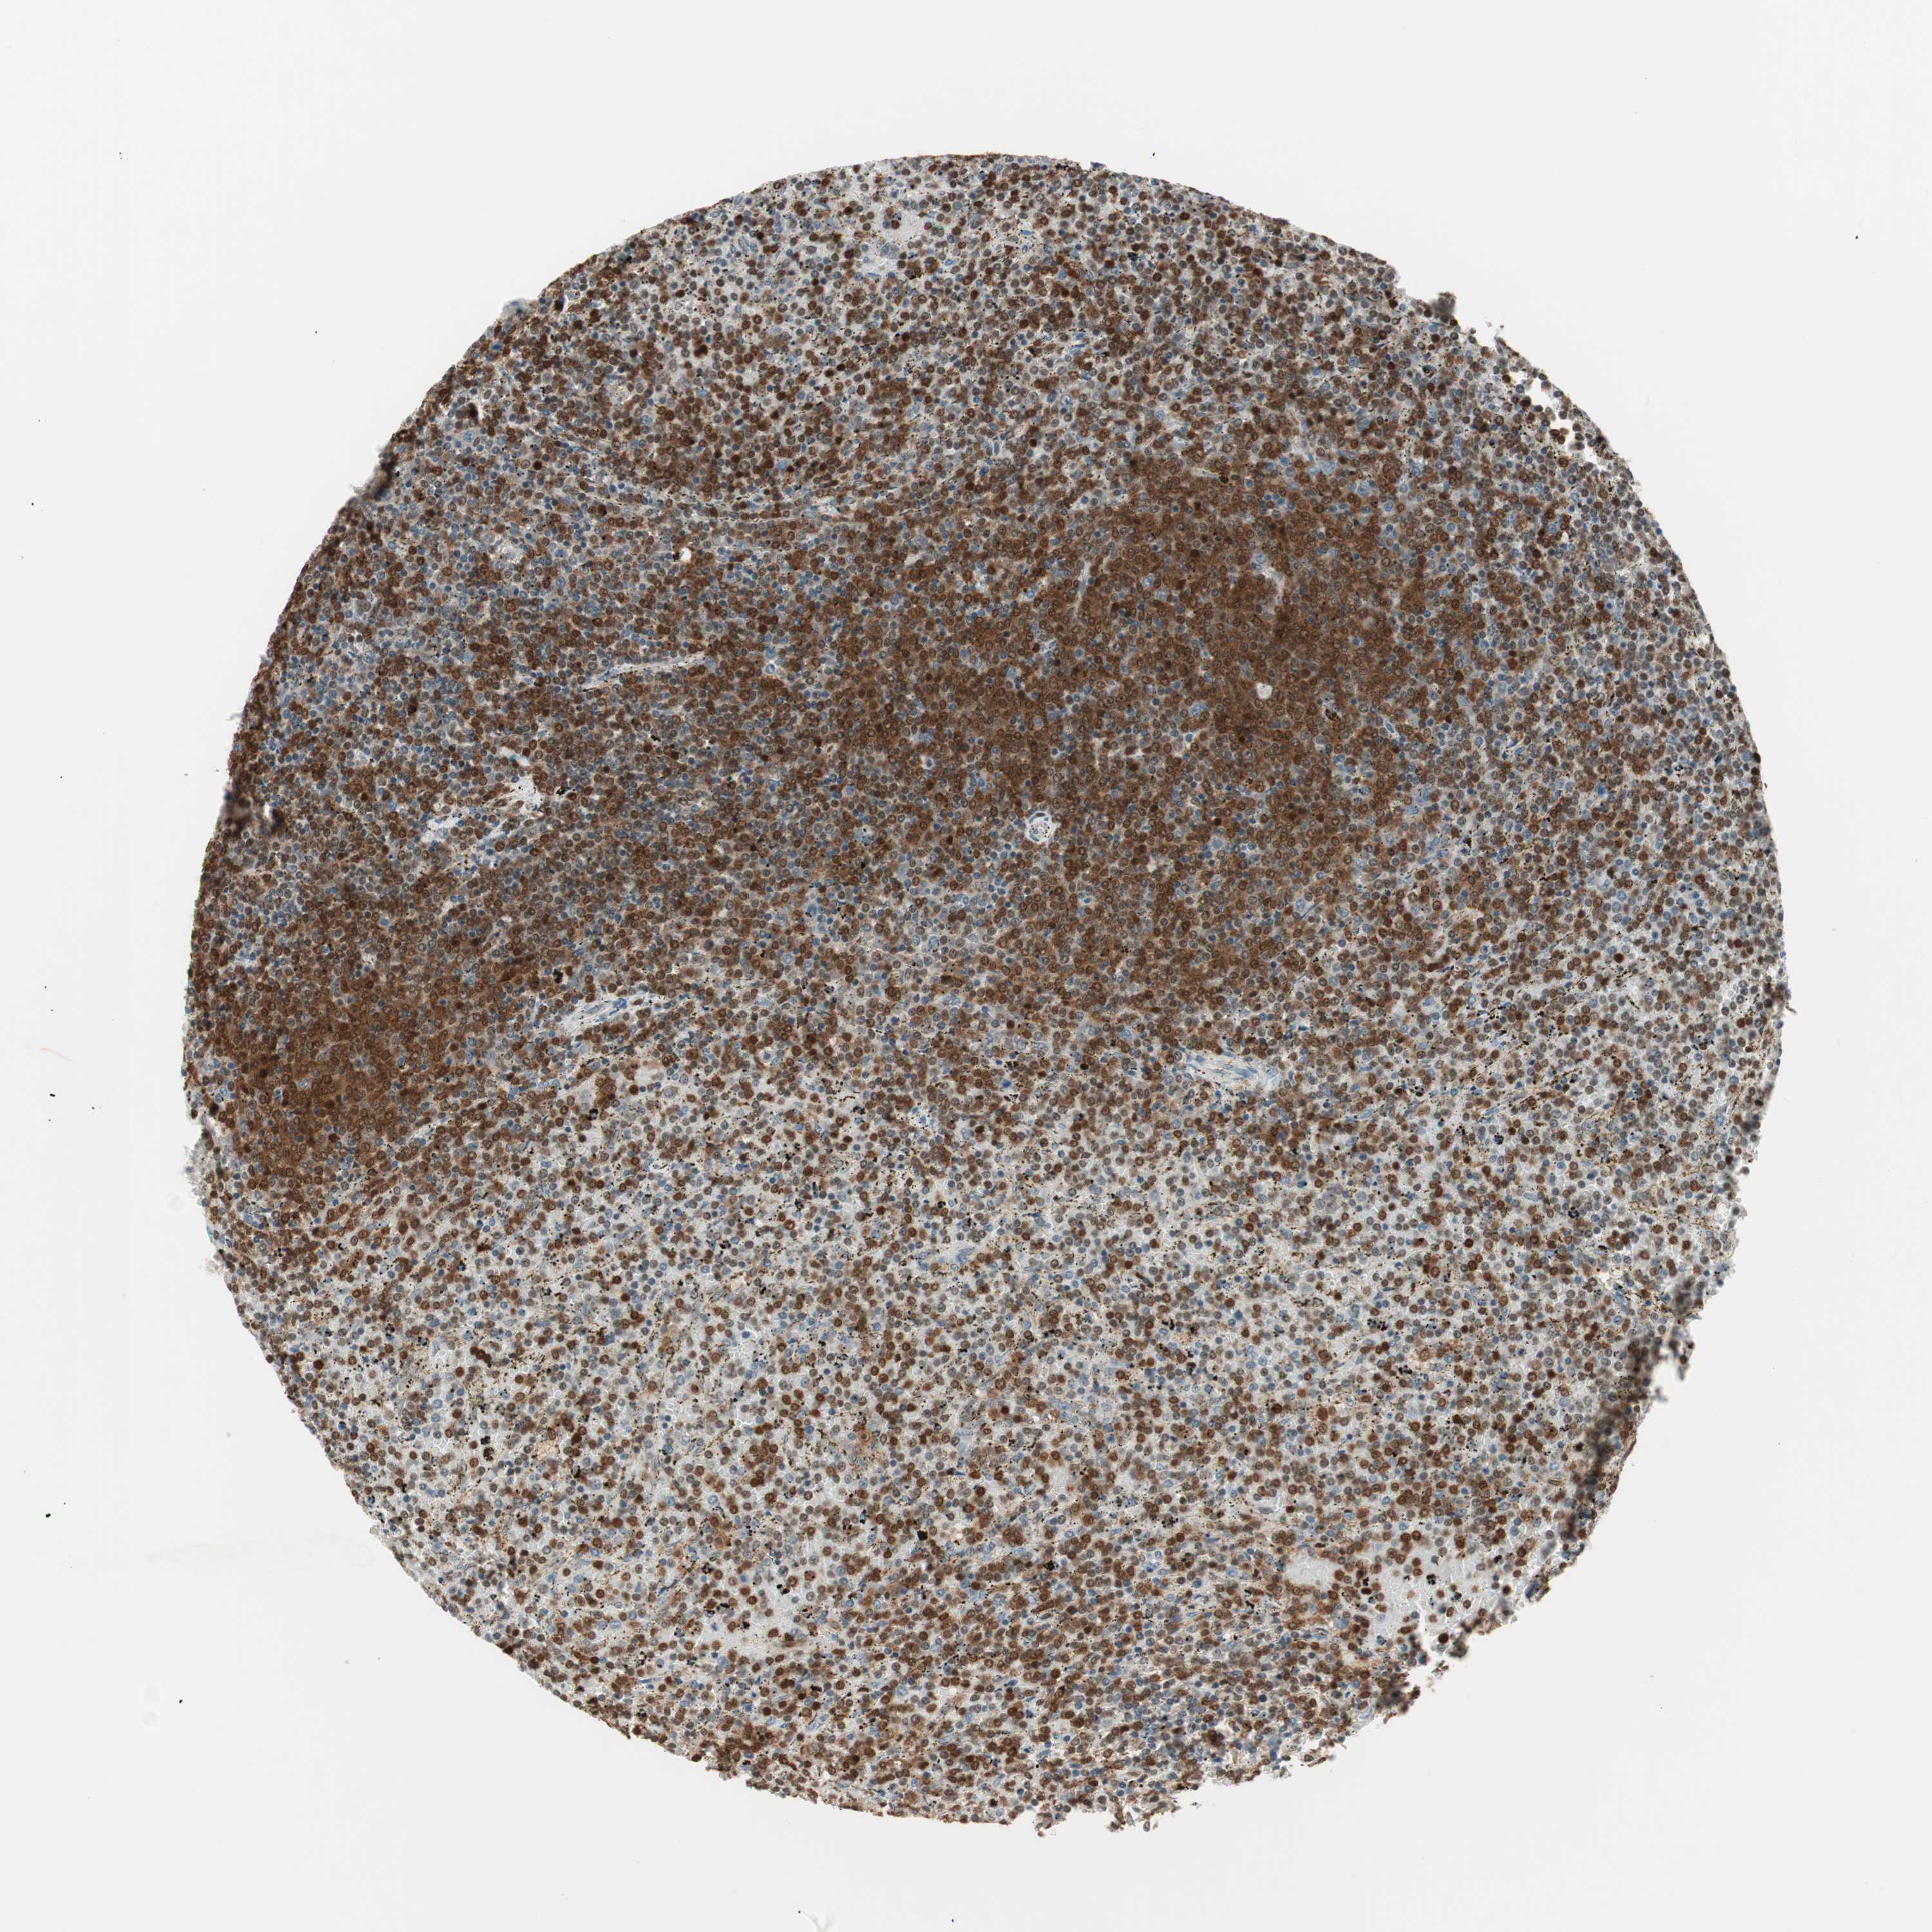

CANCER LYMPHOMA Show tissue menu

LYMPHOMA - Protein expressioni

A mouse-over function shows sample information and annotation data. Click on an image to view it in a full screen mode. Samples can be filtered based on level of antibody staining by selecting one or several of the following categories: high, medium, low and not detected. The assay and annotation is described here.

Antibody stainingi

Antibody staining in the annotated cell types in the current human tissue is reported as not detected, low, medium, or high, based on conventional immunohistochemistry profiling in selected tissues. This score is based on the combination of the staining intensity and fraction of stained cells.

Each image is clickable and will lead to virtual microscopy that enables deeper exploration of all samples and also displays staining intensity scores, fraction scores and subcellular localization as well as patient and tissue information for each sample.

Antibody HPA003909

Antibody CAB009021

Staining

High

Medium

Low

Not detected

Intensity

Strong

Moderate

Weak

Negative

Quantity

>75%

75%-25%

<25%

None

Location

Nuclear

Cytoplasmic/membranous

Cytoplasmic/membranous,nuclear

Hodgkin's disease, NOS

Malignant lymphoma, non-Hodgkin's type, Low grade

Malignant lymphoma, non-Hodgkin's type, High grade